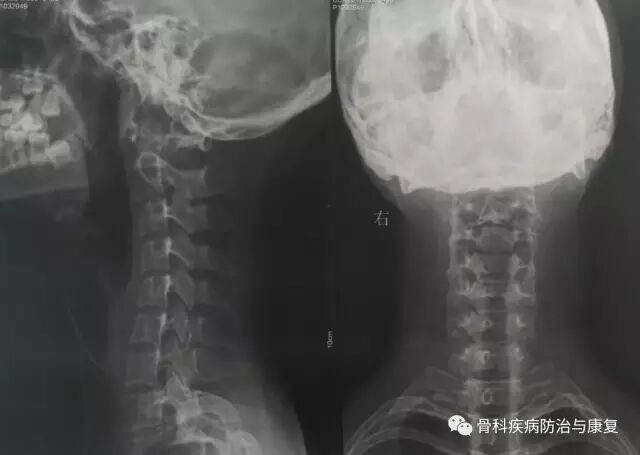

颈椎反弓的正侧位X片

通过患者小黄对症状的描述,我给小黄拍了一个颈椎的X光片,X诊断结果提示:“颈椎反弓”。小黄拿到检查报告后心里就一直犯嘀咕,急匆匆的跑到我的诊室呼喊到:

颈椎反弓是一种常见颈椎病。正常颈椎呈现“C”形向前的生理弧线,它既保证了颈椎活动的高度灵活性,又减轻了颈椎间盘的重力负荷,使颈椎处于最佳的力线状态下工作。如果没有生理弯曲,颈椎会出现僵直,甚至向相反的方向弯曲,就称为颈椎反弓。